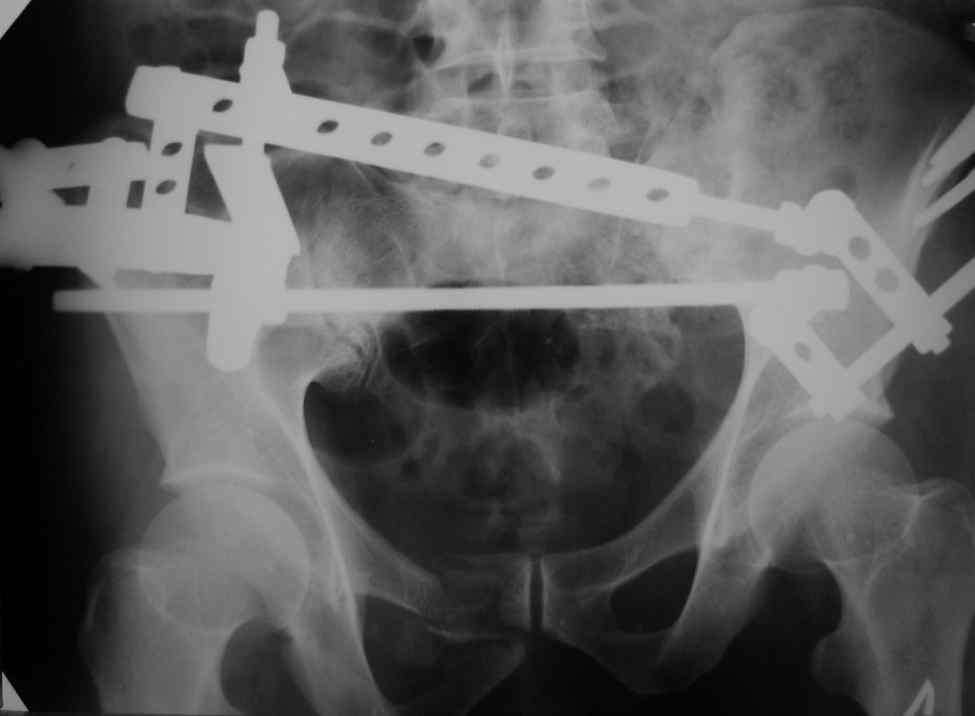

Снимки вот